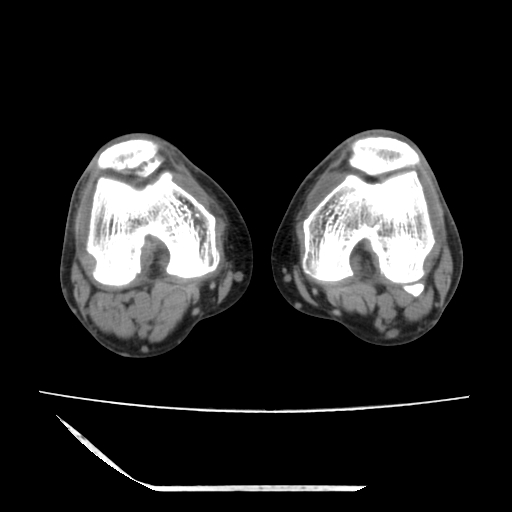

标题: CT13225:老年男性,左膝关节疼痛数月;请各位老师讨论。 [打印本页]

标题: CT13225:老年男性,左膝关节疼痛数月;请各位老师讨论。

骨质增生,骨性关节面硬化,关节积液,考虑退行性骨关节病

关节腔内少量积液,关节面退变。

双膝退变

骨质增生,骨性关节面硬化,关节间隙失常,关节积液,考虑退行性骨关节病.

骨质增生,骨性关节面硬化,关节积液,考虑退行性骨关节病。

这是由于两侧的肌肉不对称所致,加上扫描的平面也有些差异。请看示意图:

这个病例诊断:退行性骨关节炎